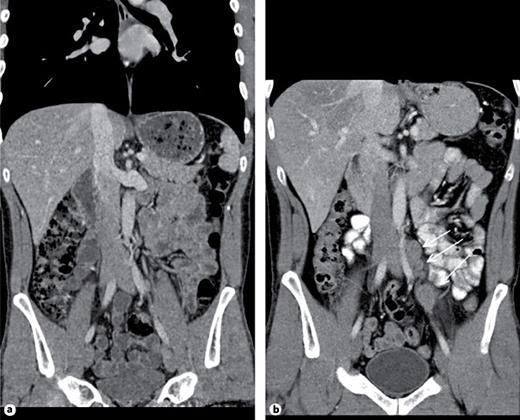

1st patient: this 43-year-old man presented with left-sided testicular discomfort. Contrast-enhanced scrotal ultrasonography demonstrated unspecific irregularities of the intratesticular echo pattern (Fig. 1). Scrotal MRI was likewise inconclusive. The classical serum tumour markers were all in the normal range. Therefore, the patient was put on a surveillance schedule. As the patient moved to another city, he was lost to follow-up. But, enquiries disclosed that orchiectomy for classical seminoma (pT1, clinical stage [CS] 1) was performed on him at another institution 4 months after our primary assessment. The serum level of miR371a-3p at the time of primary examination was RQ = 39.45 which is much higher than the normal range. Knowledge about the elevated miR-level would clearly have changed decision-making. No follow-up measurements of miR371a-p were available.